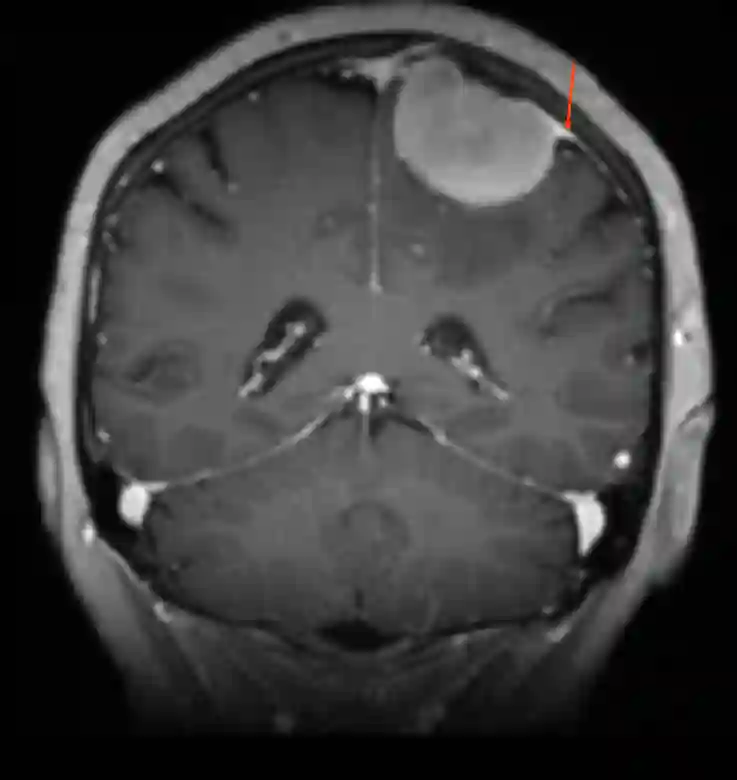

Das Dural Tail Zeichen ist ein radiologisches Zeichen, welches im MRT und teilweise auch im CT gesehen werden kann. Es beschreibt die Anhaftungsstelle, welche sich bildgebend als Ausläufer einer Raumforderung an der Dura mater zeigt. Das Dural Tail ist beispielsweise typischerweise bei Meningeomen zu finden kann sich aber auch bei anderen Raumforderungen wie beispielsweise Metastasen zeigen1 2.

Dural Tail Zeichen bei einem Meningeom (roter Pfeil).